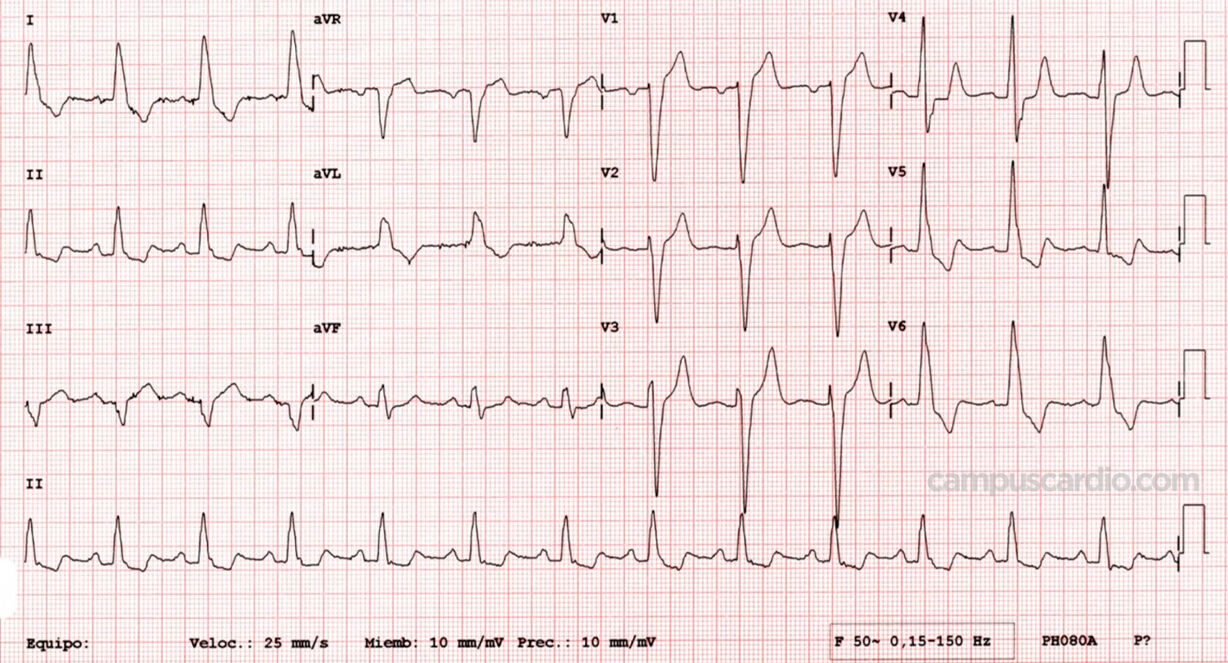

| ¿Qué se debe valorar en un electrocardiograma de un paciente con IC? |

Taquicardia, arritmias como FA, buscar infartos anteriores o bloqueos de rama izquierda o AV, identificar hipertrofia ventricular izquierda